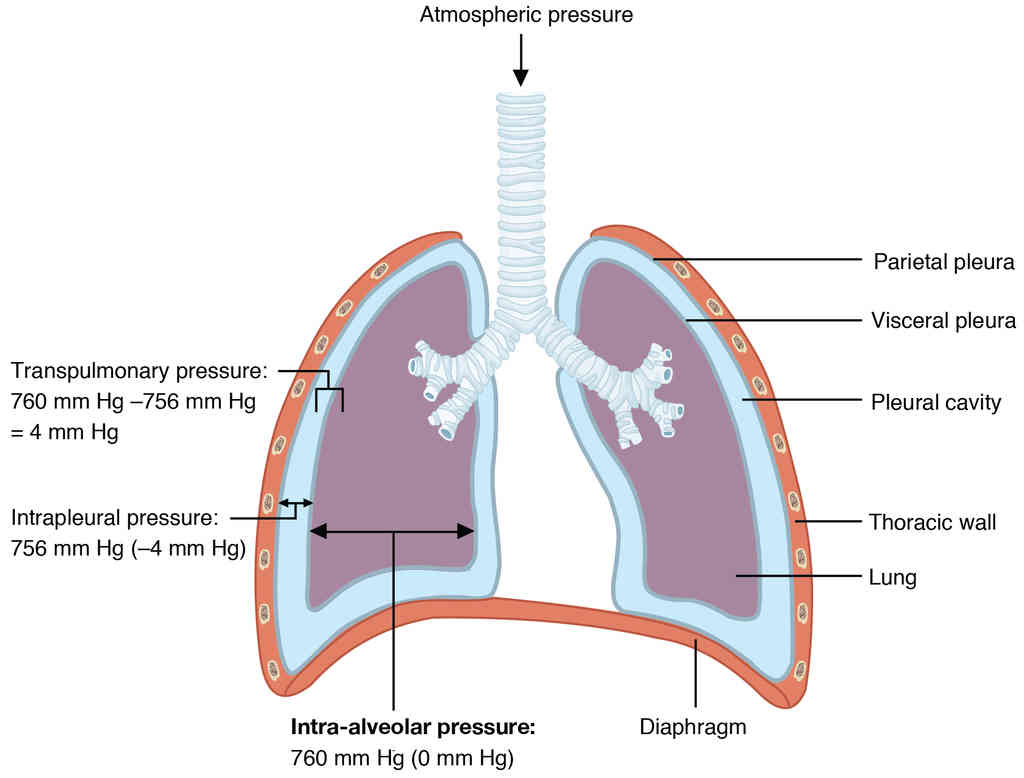

Anatomy, Physiology and Histology

This page is under construction. For now, it is just a resource of the images found in the OpenStax Anatomy and Physiology Handbook. It wil slowly change into a revision tool. Each slide has a number. Use this to refer to the slide. When completed, it will have an unlabelled section, with labelled slides in parallel. On the unlabelled slides, write your answer and use the labelled slide to assess yourself. Keep track by also noting the number on each slide. Improvement at each attempt is important, more so than full marks on a first attempt.